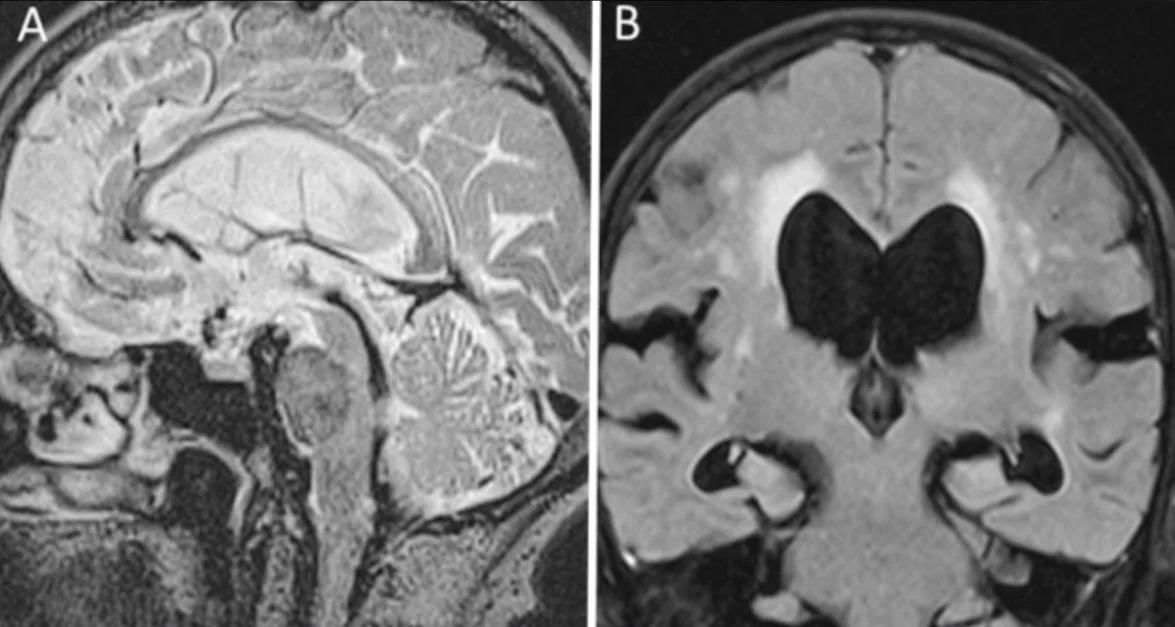

Join us at the Queen Square Simulation Centre for a hands-on neuro-oncology course focused on the practical use of modern surgical adjuncts in brain tumour surgery.

Hands-on simulation course on modern brain tumour surgery - Anatomy, techniques, and technologies.